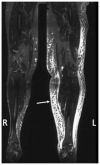

Background: Clinical examination and lymphoscintigraphy are the current standard for investigating lymphatic function. Magnetic resonance imaging (MRI) facilitates three-dimensional (3D), nonionizing imaging of the lymphatic vasculature, including functional assessments of lymphatic flow, and may improve diagnosis and treatment planning in disease states such as lymphedema.

Results: From 612 identified articles, 43 articles were included and their protocols and results summarized. Field strength was 1.5 or 3.0 T in all studies, with 25/43 (58%) employing 3.0 T imaging. Most commonly, imaging of the peripheries, upper and lower limbs including the pelvis (32/43, 74%), and the trunk (10/43, 23%) is performed, including two studies covering both regions. Imaging protocols were heterogenous; however, T2 -weighted and contrast-enhanced T1 -weighted images are routinely acquired and demonstrate the lymphatic vasculature. Edema, vessel, quantity and morphology, and contrast uptake characteristics are commonly reported indicators of lymphatic dysfunction.

Data conclusion: MRL is uniquely placed to yield large field of view, qualitative and quantitative, 3D imaging of the lymphatic vasculature. Despite study heterogeneity, consensus is emerging regarding MRL protocol design. MRL has the potential to dramatically improve understanding of the lymphatics and detect disease, but further optimization, and research into the influence of study protocol differences, is required before this is fully realized.